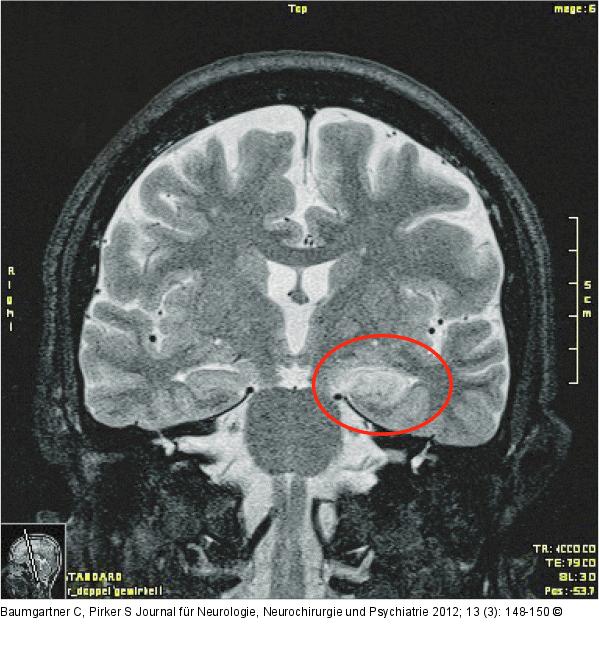

Abbildung 1: Limbische Enzephalitis MRT bei limbischer Enzephalitis: mediotemporale T2-Hyperintensität links. |

MRT bei limbischer Enzephalitis: mediotemporale T2-Hyperintensität links. |